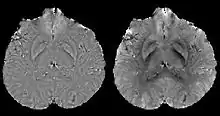

Calculation Of Susceptibility through Multiple Orientation Sampling (COSMOS)[11][12]

COSMOS solves the inverse problem by oversampling from multiple orientations.[11] COSMOS utilizes the fact that the zero cone surface in the Fourier domain is fixed at the magic angle with respect to the B0 field. Therefore, if an object is rotated with respect to the B0 field, then in the object's frame, the B0 field is rotated and thus the cone. Consequently, data that cannot be calculated due to the cone becomes available at the new orientations.

COSMOS assumes a model-free susceptibility distribution and keeps full fidelity to the measured data. This method has been validated extensively in in vitro, ex vivo and phantom experiments. Quantitative susceptibility maps obtained from in vivo human brain imaging also showed high degree of agreement with previous knowledge about brain anatomy. Three orientations are generally required for COSMOS, limiting the practicality for clinical applications. However, it may serve as a reference standard when available for calibrating other techniques.